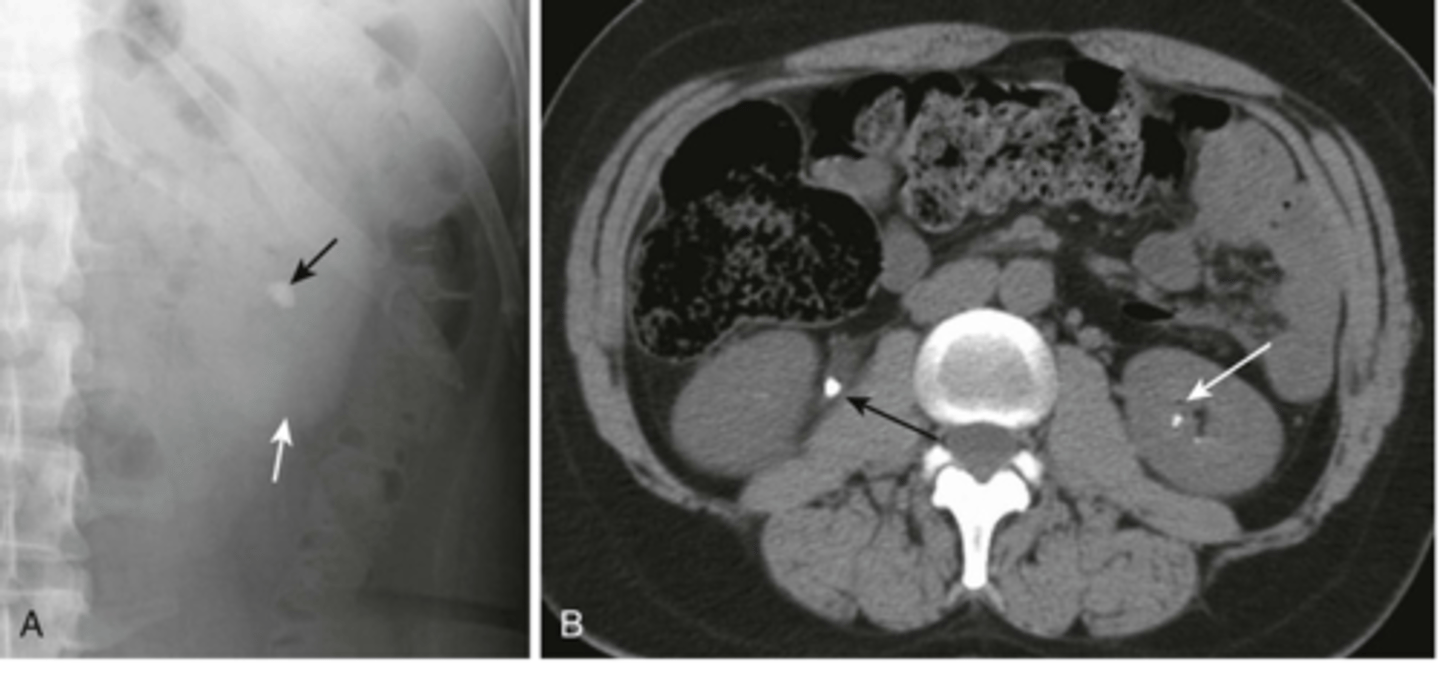

renal calculi

stone in R ureter, stone in L kidney